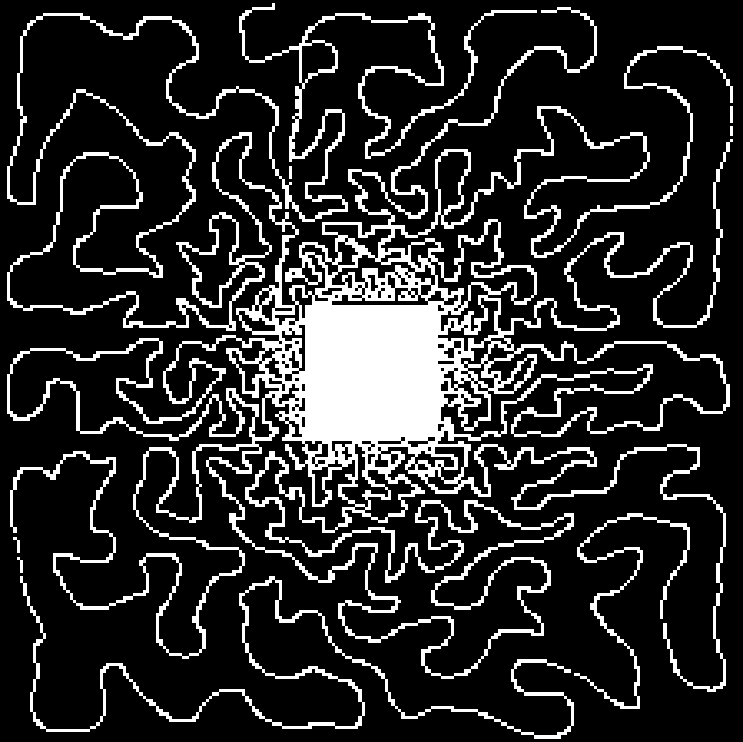

In this experiment, we considered a 2D -space () corresponding to an axial slice. We considered five sampling strategies, depicted in Fig. 2(first row): a classical EPI coverage used as reference (a); a TSP-based sampling trajectory parameterized using optimal control (b); two projected TSP-based trajectories, one with the same number of samples collected as in (b) () (c) and the other with the same scanning time as in (b) (62 ms) (d); a variable density spiral trajectory for comparison purpose in terms of time and sampling ratio (e).

As expected, the reconstruction results shown in Fig. 2(g,h) are really close, since the number of collected samples is the same, and the sampling densities are similar. However, in this comparison the gain in traversal time is significant (one half). In contrast, the longer and smoothed TSP depicted in Fig. 2(d) allows us to improve image reconstruction (1 dB gain) as illustrated by Fig. 2(i) while keeping the same acquisition time as in Fig. 2(b). For comparison purposes, we implemented spiral acquisition which consists of replacing steps (ii)-(iii) in the above mentioned sampling strategy by a spiral with density proportional to , projected onto the set of constraints. This strategy doubles the acquisition time (118 ms compared to 62 ms) whereas the acceleration factor was larger ( vs. ). In this experimental context (regridding and variable density spiral), the spiral is not appealing compared to EPI acquisition, since it is time consuming and degrades the image quality.

In each of these reconstructions, the major vessels can be recovered, although the smallest ones can only be seen for . Finally, the best compromise between acquisition time and reconstruction quality is achieved using the specific combination of TSP-based sampling and our projection algorithm onto the set of constraints shown in Fig. 2(d).

| ms () | ms () | ms () | ms () | ms () |

| Reference | PSNR = 25.9 dB | PSNR = 25.5 dB | PSNR = 26.9 dB | PSNR = 26.8 dB |